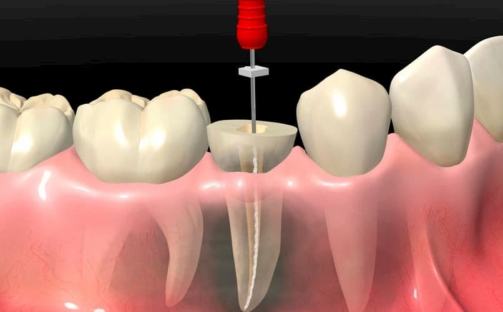

Endodoncia: el tratamiento para salvar tu diente

Descubre qué es una endodoncia, cuándo se indica y cómo puede ayudarte a conservar tu diente natural sin dolor.